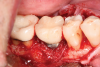

After local anesthesia was administered, full-thickness flaps were elevated from the buccal and lingual aspects of tooth No. 27 to the distobuccal and lingual aspects of tooth No. 31. Removal of granulomatous tissue from the implant site allowed visualization of a combination lesion with two walls at the distal and two to three walls at the mesial with a circumferential configuration on the lingual (Figure 12). The surface was initially treated with a 50% solution of citric acid for 30 seconds, which was burnished on with cotton pellets followed by thorough rinsing with sterile saline. This was followed by implantoplasty using 12-fluted followed by 30-fluted surgical-length finishing burs that provided access to the base of the defect. Because the crown was cemented, which obviated access, a matte-like surface could not be achieved; thus, the goal was to reduce the threads and remove the outer affected surface to expose fresh titanium (Figure 13). At this stage, the implant was wiped again with citric acid and rinsed with sterile saline.

Fig 12. The lesion was visualized upon flap reflection. A three- to two-wall lesion on the mesial wrapped to the lingual, while the distal had a two-wall lesion that also extended to the lingual as a moat.

Figure 12